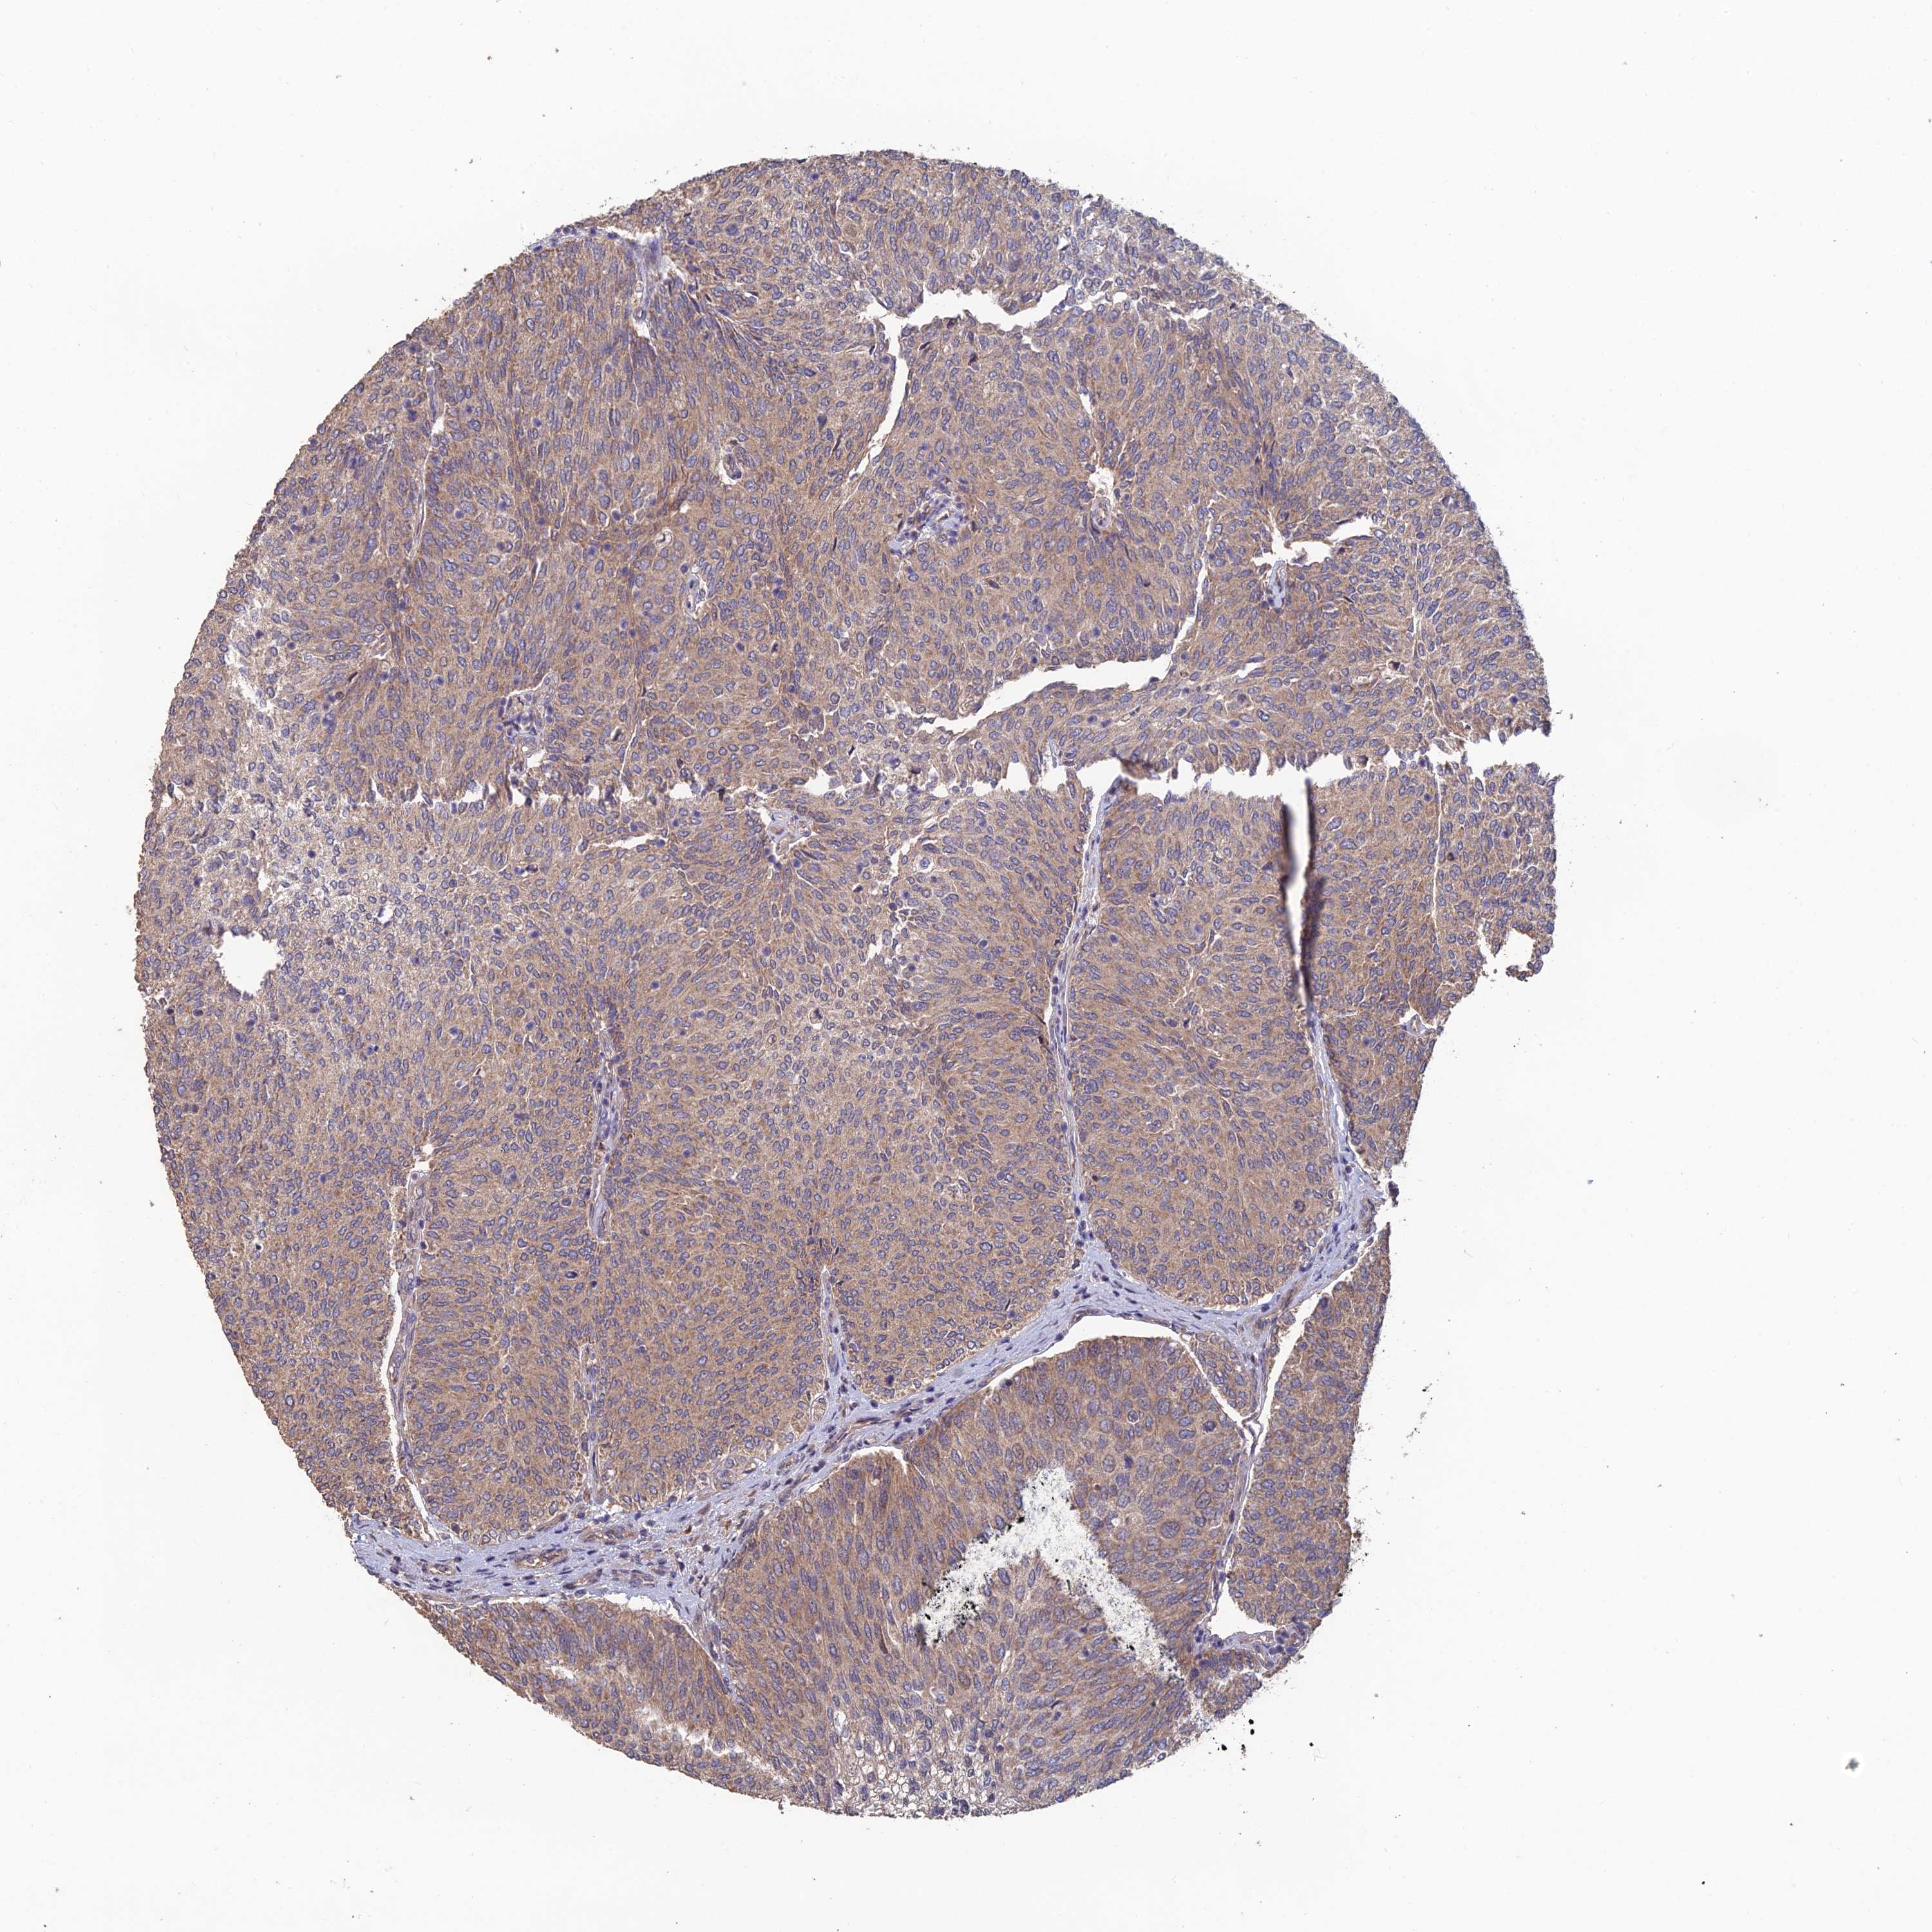

UROTHELIAL CANCER - Protein expressioni

A mouse-over function shows sample information and annotation data. Click on an image to view it in a full screen mode. Samples can be filtered based on level of antibody staining by selecting one or several of the following categories: high, medium, low and not detected. The assay and annotation is described here.

Note that samples used for immunohistochemistry by the Human Protein Atlas do not correspond to samples in the TCGA dataset.

Antibody stainingi

Antibody staining in the annotated cell types in the current human tissue is reported as not detected, low, medium, or high, based on conventional immunohistochemistry profiling in selected tissues. This score is based on the combination of the staining intensity and fraction of stained cells.

Each image is clickable and will lead to virtual microscopy that enables deeper exploration of all samples and also displays staining intensity scores, fraction scores and subcellular localization as well as patient and tissue information for each sample.

Antibody HPA042295

Staining

High

Medium

Low

Not detected

Intensity

Strong

Moderate

Weak

Negative

Quantity

>75%

75%-25%

<25%

None

Location

Nuclear

Cytoplasmic/membranous

Cytoplasmic/membranous,nuclear

Urothelial carcinoma, High grade

Urothelial carcinoma, Low grade